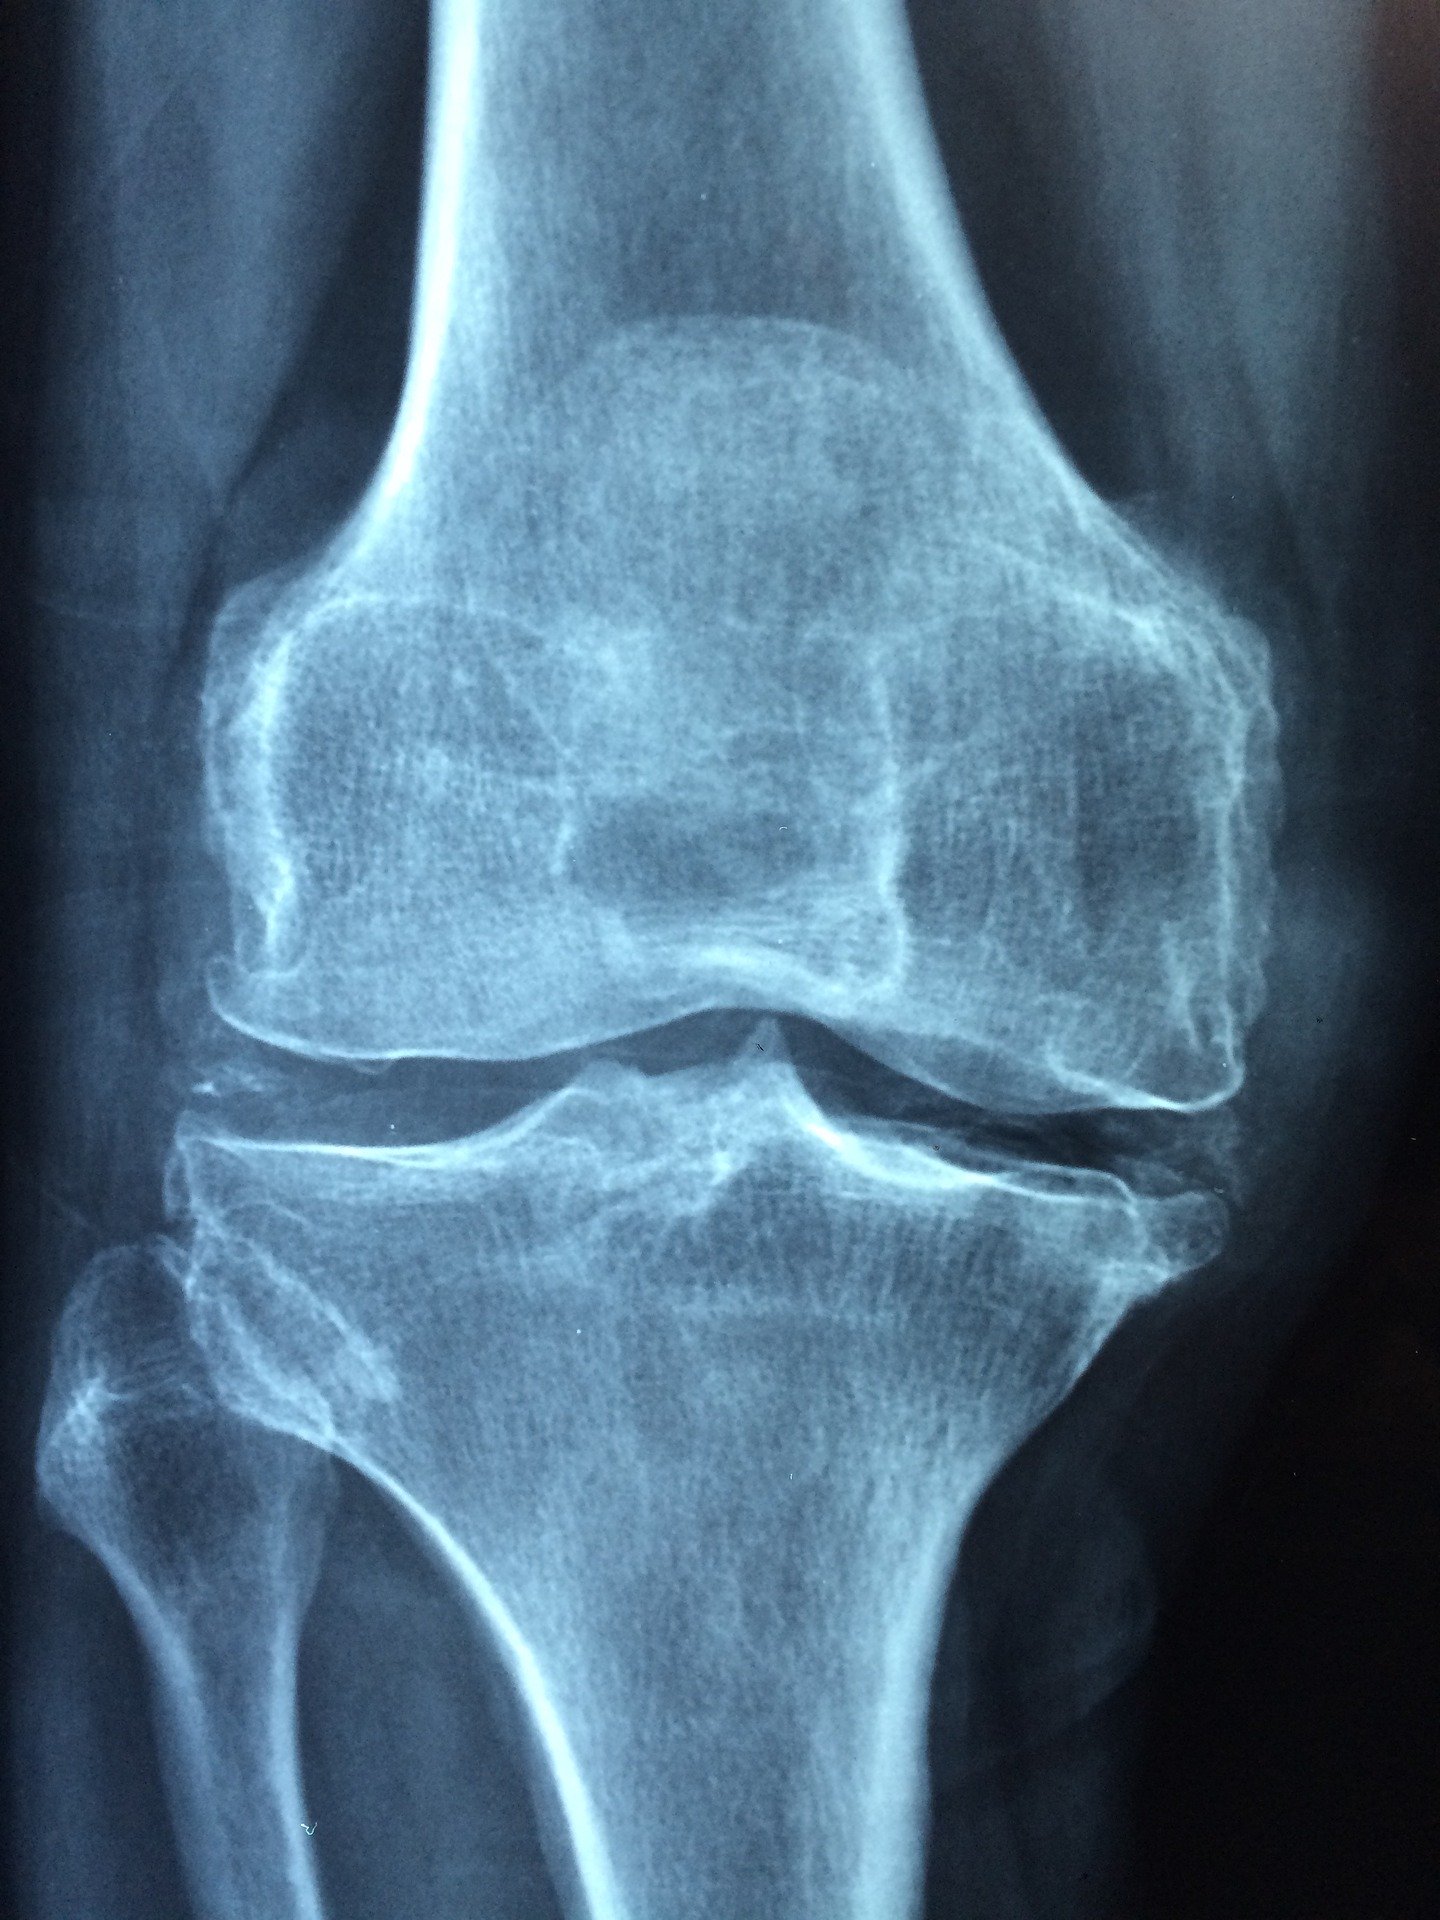

- Arthrose

Cette pathologie s’avère également être une origine fréquente des lésions qui peuvent atteindre les racines nerveuses causant ainsi la sciatique. Elle se manifeste par la formation des petites pointes osseuses qui compriment les racines nerveuses.

Si la douleur dure plus de trois semaines, des examens complémentaires peuvent être nécessaires pour confirmer la présence, mais aussi la gravité de la sciatique. Il peut entre autres prescrire une radiographie, un scanner, une la tomodensitométrie ou encore une IRM (imagerie par résonance magnétique). Ces examens sont surtout effectués pour vérifier la présence d’une hernie discale.